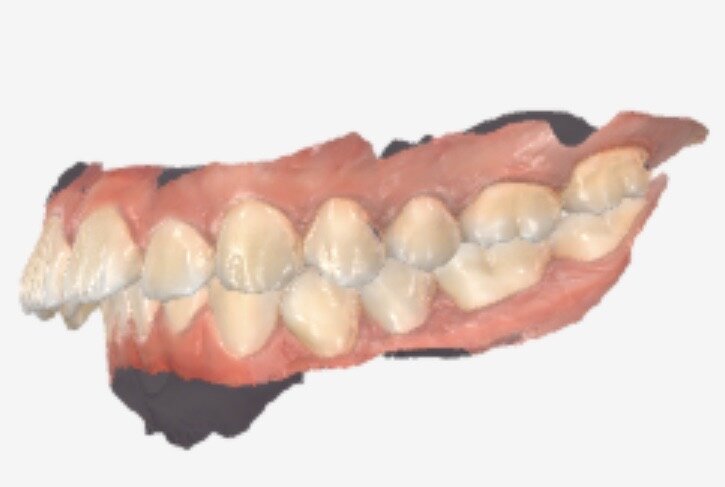

I have a 9mm overbite and ive went to 3 places (2 dentists and one ortho) and theyve all reccomended i pull teeth due to the large overbite and the ortho said that using a palette expander would not give me the space i need to fit my teeth

Must i really pull teeth with such a severe overbite or is there another solution to fix my teeth without risking ruining my side profile

(Ive attached 3 angles of 3d scans of my teeth more can be provided if asked)

Must i really pull teeth with such a severe overbite or is there another solution to fix my teeth without risking ruining my side profile

(Ive attached 3 angles of 3d scans of my teeth more can be provided if asked)